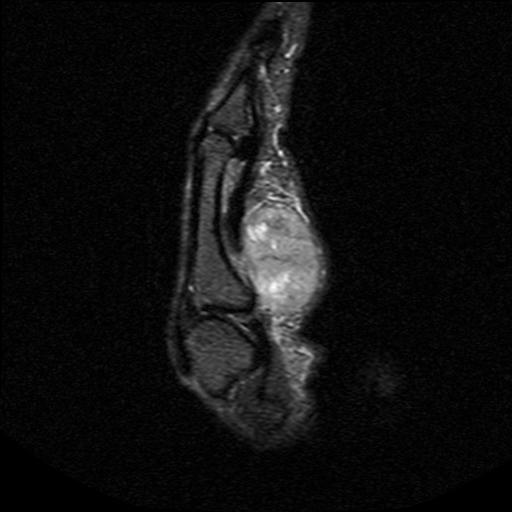

6. Synovial Chondromatosis

Diffuse swelling

May have calcification